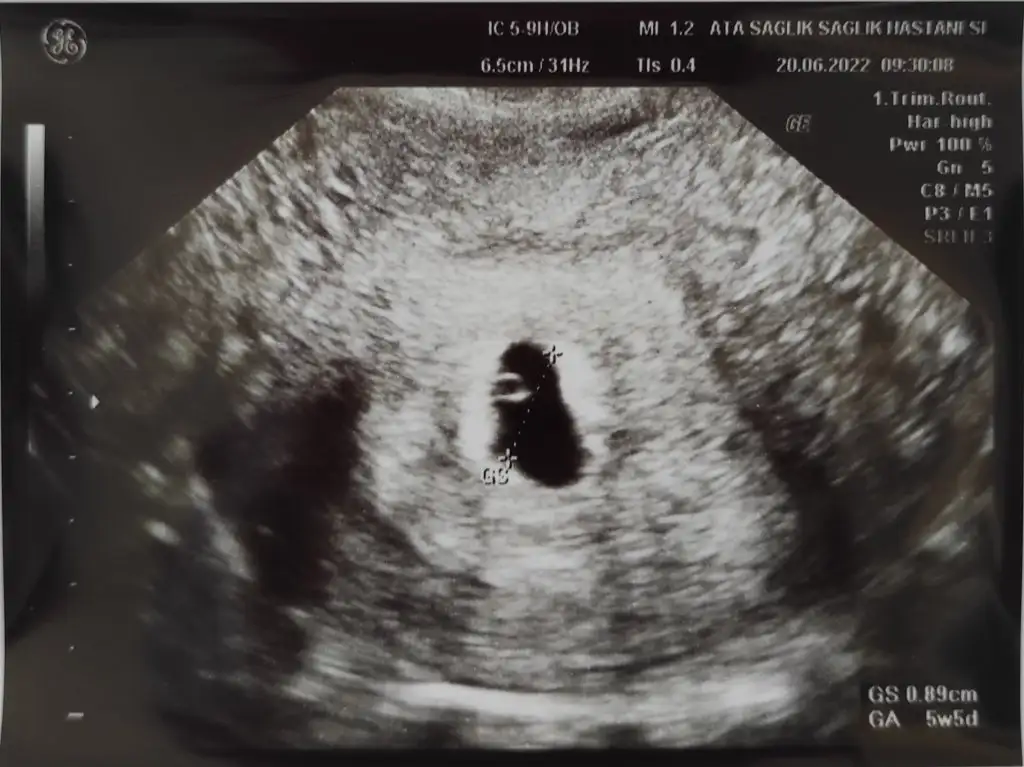

yolk sac daha çok büyük bir sonraki görüntüne yorum yapmak doğru olır